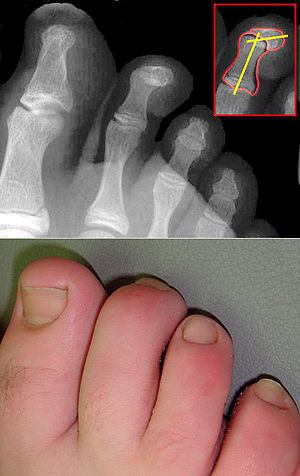

Die Form einer Hammerzehe (Digitus malleus) ergibt sich durch die permanente krallenartige Beugung einer Zehe. Man unterscheidet flexible und fixierte Hammerzehen. Sie ist differentialdiagnostisch von der Kamptodaktylie abzugrenzen und meistens aufgrund der Verwendung ungeeigneten Schuhwerks mechanisch bedingt. Auch neurologische Erkrankungen können zu diesem Symptom führen.

Die Hammerzehe stellt die häufigste Zehendeformation dar. Es besteht eine Beugekontraktur im Mittelgelenk (PIP = proximales Interphalangealgelenk), seltener (auch) im Endgelenk (DIP = distales Interphalangealgelenk). Die Krallenzehe charakterisiert sich im Unterschied zur Hammerzehe durch eine Luxation oder Subluxation im Zehengrundgelenk (MTP = Metatarsophalangealgelenk) im Sinne der Überstreckung (Hyperextension).

Klinik und Diagnostik

Druckbeschwerden bei Hühneraugen, Schwielen, Schmerzen unter den Mittelfußköpfchen, Schuhkonflikte, ästhetische Störung. Die Bestimmung der Beweglichkeit, der Zehenlänge und der Abstände zwischen den Zehen ist für die Auswahl des operativen Verfahrens wichtig.